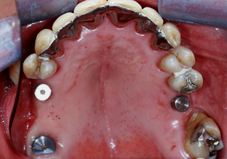

Arcade maxillaire avant traitement orthodontique, séquelles de maladie parodontale

Après traitement orthodontique et réalisation d’une attelle coulée collée (courtoisie Dr Patrick Fournier)